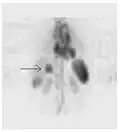

ОФЭКТ-сканирование печени ядерной медицины с мечеными технецием-99m аутологичными эритроцитами. Очаг высокого поглощения (стрелка) в печени соответствует гемангиоме.